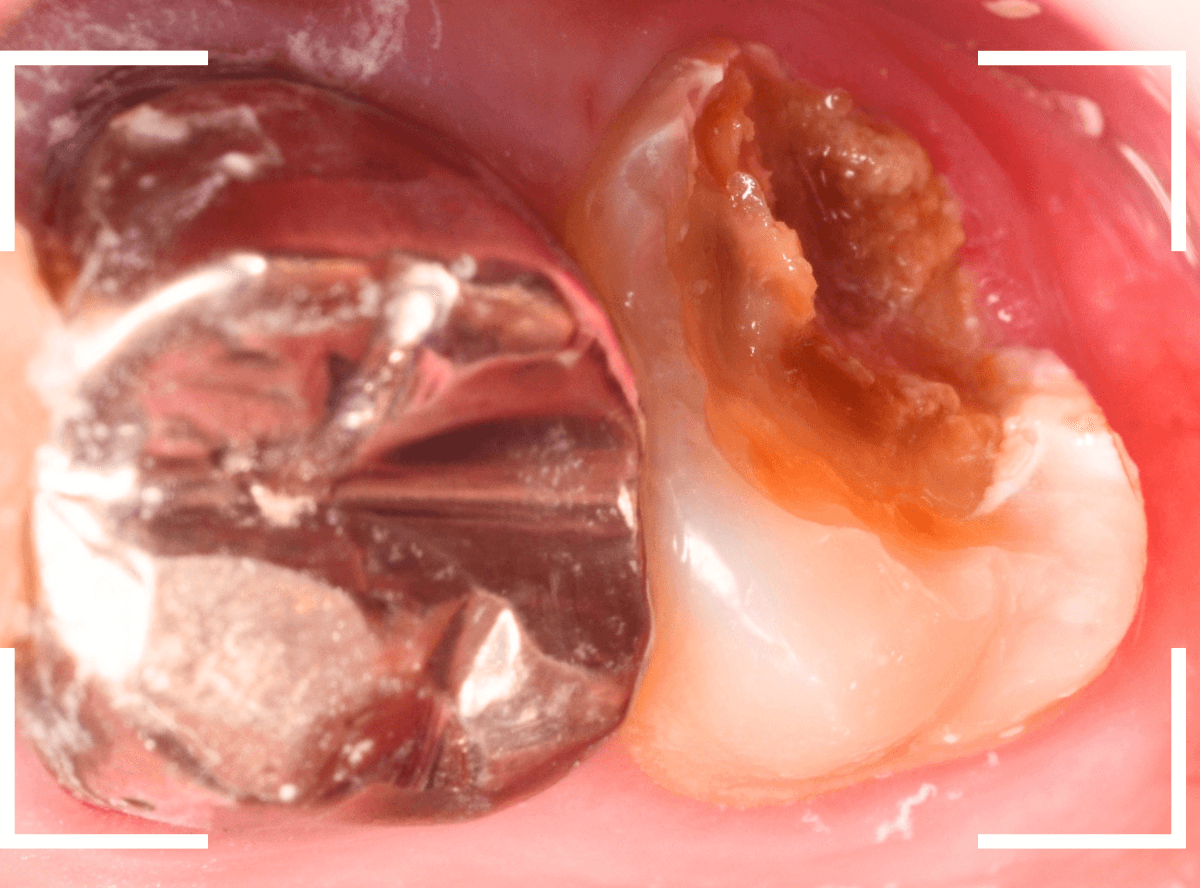

Case.12 下の一番奥の歯が、奥からひどい虫歯

「下の一番奥の歯が痛い」という訴えで来院された患者さんの例です。

一見では、特に問題ないように見えます。

治療を開始します。

歯の奥の部分を少し削ると、虫歯が出てきました。

慎重に虫歯を除去します。

歯肉ラインの下まで虫歯が進行しているため、虫歯の上に歯肉が広がっており、虫歯の見分けがつきづらい状況になっています。

虫歯を取り残さないように、余分な歯肉を除去します。

電気メスで、虫歯周囲の歯肉を除去後、全ての虫歯を除去しました。

虫歯は深かったですが、なんとか神経寸前のところで食い止められました。

神経を保護するお薬をつめて、セメントで蓋をしてしばらく経過観察します。

経過観察後、痛みがない事が確認できれば、つめものを作製します。